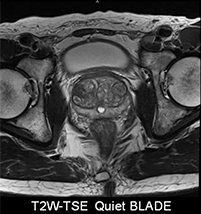

<SIEMENS社製MAGNETOM skyra3.0テスラ(T)MRIのご紹介>

3.0テスラの強い磁場で検査することにより、より強い信号が得られるため情報量が多く、より高分解能(高画質)な画像、より短時間撮影が可能となりました。

多彩な専用コイルで高画質

頭部や脊椎、乳房専用コイル、肩関節専用、膝関節専用、手指関節専用など撮像部位に応じた多彩なコイルを用意しています。

[膝関節撮像例]

静音技術「Quiet Suite」搭載

新しいノイズリダクション機構“Quiet Suite”は、高画質を担保しながら、従来より70%以上のノイズリダクションを実現しました。ノイズを抑えることにより静かな検査が可能になり、より患者様の心理的負担を軽減し、やさしい検査を実現します。検査中は、MRIからの騒音から聴覚器官への刺激を軽減するためヘッドフォン を装着し、音楽を聴きながらリラックスした状態で検査を受けて頂くことが可能です。